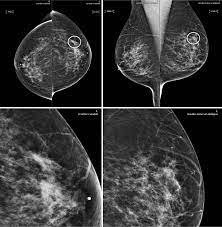

X Ray Mammogram Showing Evidence Of Breast Cancer Stock Image M122 0050 Science Photo Library from media.sciencephoto.com But it's not uncommon that they see something that looks like it might be cancer —a finding that could end up being completely normal, but that needs to be further tested to be sure. What does cancer look like on a mammogram? The tumor cells don't stay within the clear borders of the mass, but instead invade the nearby breast tissue. This type of cancer also changes the appearance of your breasts. This can make it harder for your radiologist to spot signs of breast cancer, since dense tissue and tumors both look white in mammogram images. The look of breast cancer on a mammogram a tumor or lump will appear as a focused white area on the mammogram. A mammogram can show breast changes such as calcifications, masses, or other symptoms that might be cancer. Dr sarah jarvis mbeif a mammogram is abnormal, further tests will be needed.

Invasive breast cancer can appear as a white patch or mass on a mammogram. The tumor cells don't stay within the clear borders of the mass, but instead invade the nearby breast tissue. You may notice dimpling or pitting, and the skin on your breast. A rash isn't the only visual symptom of inflammatory breast cancer. Regular mammograms are the best tests doctors have to find breast cancer early. In a normal breast, a mammogram shows normal skin dark grey fat and lighter grey breast tissue. According to the american cancer society (acs), the most common sign of breast cancer is a new lump or mass in the breast. How can mammograms be used? Cancers may be seen as masses (like a ball, but usually with an irregular shape), areas of asymmetry that resemble normal tissue, calcifications (white specks), and/or areas of architectural distortion (imagine the puckering caused by pulling a thread in a piece of fabric). In this mammogram image, the breast calcifications are in ductal patterns. Healthy mammograms can still vary in appearance. It is important to bear in mind that most women who are asked to come back after. Any area that does not look like normal tissue is a possible cause for concern.

Ibc symptoms are caused by cancer cells blocking lymph vessels in the skin causing the breast to look inflamed. symptoms include breast swelling, purple or red color of the skin, and dimpling or thickening of the skin of the breast so that it may look and feel like an orange peel. What does cancer look like on a mammogram? Cancers may be seen as masses (like a ball, but usually with an irregular shape), areas of asymmetry that resemble normal tissue, calcifications (white specks), and/or areas of architectural distortion (imagine the puckering caused by pulling a thread in a piece of fabric). Tumors may be benign or cancerous. According to the american cancer society (acs), the most common sign of breast cancer is a new lump or mass in the breast. Suspicious findings include clusters of tiny microcalcifications or a density/mass with irregular or spiculated margins. Any area that does not look like normal tissue is a possible cause for concern. This can make it harder for your radiologist to spot signs of breast cancer, since dense tissue and tumors both look white in mammogram images. Breast cancer and some noncancerous (benign) breast conditions can appear white on a mammogram. This is considered an abnormal mammogram, but not necessarily one that's indicative of cancer. Invasive breast cancer can appear as a white patch or mass on a mammogram. By the time it's diagnosed, it usually has grown into the skin of your breast. What does an abnormal mammogram look like?

Ai Assisted Radiologists Can Detect More Breast Cancer With Reduced False Positive Recall Imaging Technology News from www.itnonline.com Breast cancer and some noncancerous (benign) breast conditions can appear white on a mammogram. By the time it's diagnosed, it usually has grown into the skin of your breast. The outer edges of these cells look fuzzy or spiky (called spiculated). They will look carefully at the mammogram to interpret the results. The doctor reading your mammogram will be looking for different types of breast changes, such as small white spots called calcifications, larger abnormal areas called masses, and other suspicious areas that could be signs of cancer. The appearance of normal breast tissue on a mammogram varies from person to person, and no two mammograms look the same. Cancers may be seen as masses (like a ball, but usually with an irregular shape), areas of asymmetry that resemble normal tissue, calcifications (white specks), and/or areas of architectural distortion (imagine the puckering caused by pulling a thread in a piece of fabric). According to the american cancer society (acs), the most common sign of breast cancer is a new lump or mass in the breast.

This is considered an abnormal mammogram, but not necessarily one that's indicative of cancer. The tumor cells don't stay within the clear borders of the mass, but instead invade the nearby breast tissue. The appearance of normal breast tissue on a mammogram varies from person to person, and no two mammograms look the same. Dr sarah jarvis mbeif a mammogram is abnormal, further tests will be needed. The doctor reading your mammogram will be looking for different types of breast changes, such as small white spots called calcifications, larger abnormal areas called masses, and other suspicious areas that could be signs of cancer. Regular mammograms are the best tests doctors have to find breast cancer early, sometimes up to three years before it can be felt. Mammograms will often detect areas that are more dense than normal breast tissue or that have little flecks of calcium within milk ducts. What does breast cancer look like on a mammogram? What does breast cancer look like on a mammogram? You may notice dimpling or pitting, and the skin on your breast. This can make it harder for your radiologist to spot signs of breast cancer, since dense tissue and tumors both look white in mammogram images. Any area that does not look like normal tissue is a possible cause for concern. Any area that does not look like normal tissue is a possible cause for concern.